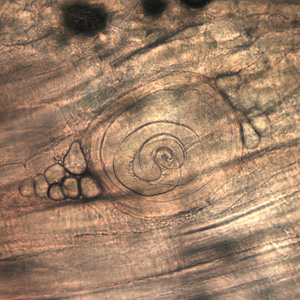

Trichinella larvae in pressed bear meat, partially digested with pepsin. The classic coil shape is visible. | |